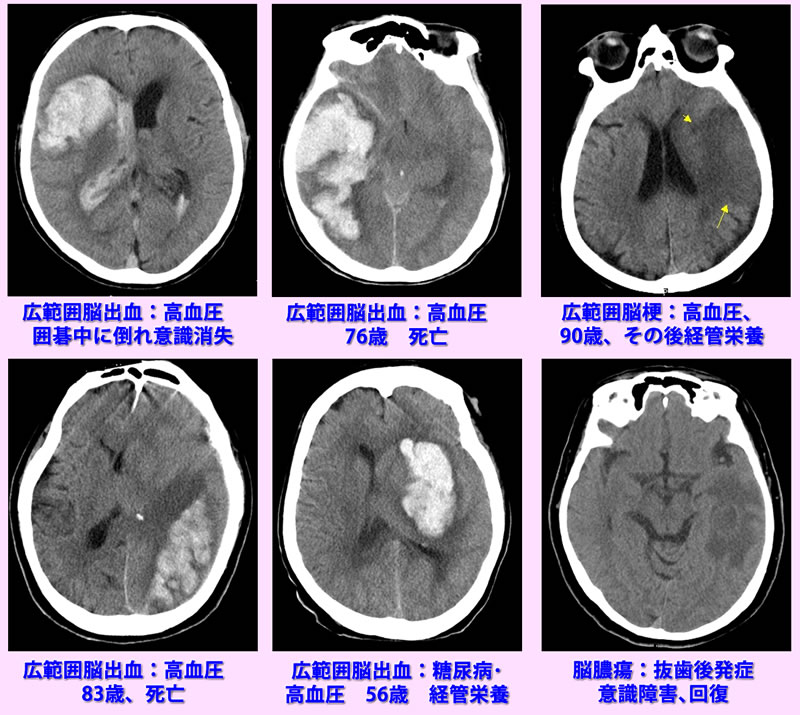

意識障害の診断

意識障害の原因には 低血糖、高アンモニア、CO2ナルコーシスなどの血液、代謝異常などや脳の器質的障害があります。後者は画像診断が有用です.下段に参考画像を示します。